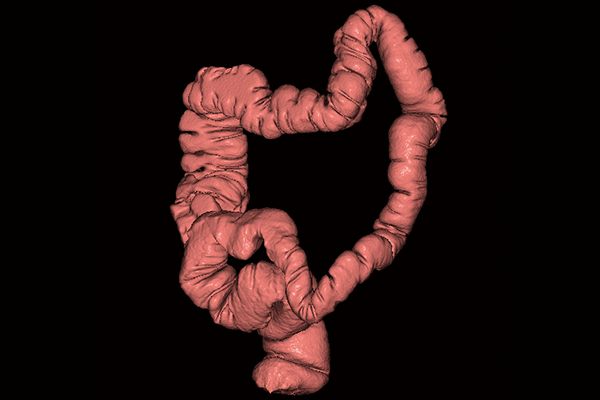

SYNAPSE 3D’s advanced image analysis technology aids clinical interpretation, reporting, and treatment planning. Especially,

automatic organ segmentation technology enables fast and effective workflow, powered by REiLI, FUJIFILM's AI brand. With

a series of high-tech applications developed in collaboration with clinical specialists, SYNAPSE 3D quickly and accurately

delivers imaging result that promotes effective care collaboration.

REiLI makes it happen to extract organs and simplify your work.

Colon

Virtual Endoscope